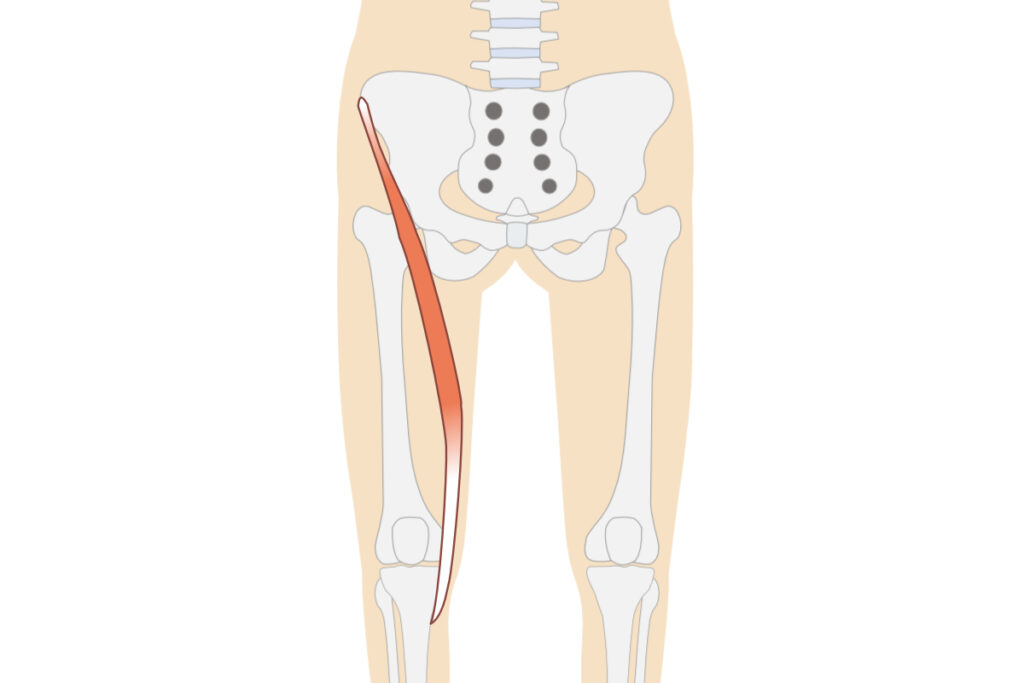

膝の痛みの原因になりやすい筋肉の例

外側広筋

大腿筋膜張筋

縫工筋

膝の痛みの原因になりやすい部位を中心に刺激

外側広筋

大腿筋膜張筋

縫工筋

刺激するポイントは個人差があり、その日の体調によっても変化します(イラストは参考図)